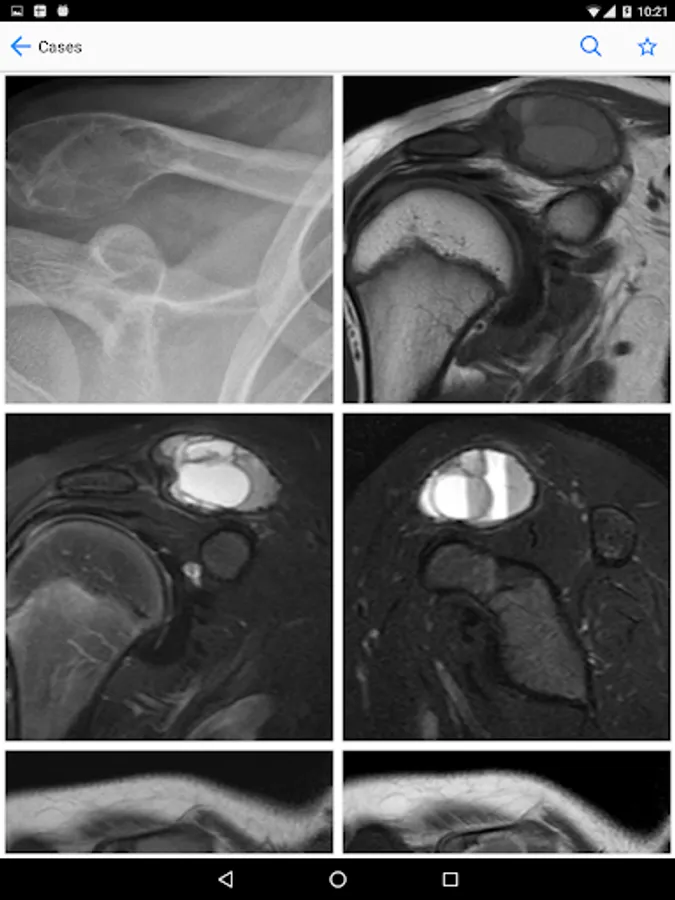

BoSTT brings the user a real experience of frequent and rare, typical and more unusual cases of bone and soft tissue tumours. Each case has a clinical history, high resolution radiology and pathology images, diagnosis, treatment and learning points.